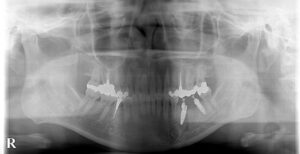

🔶矯正開始時レントゲン🔶

すでにインプラントが入っている患者様